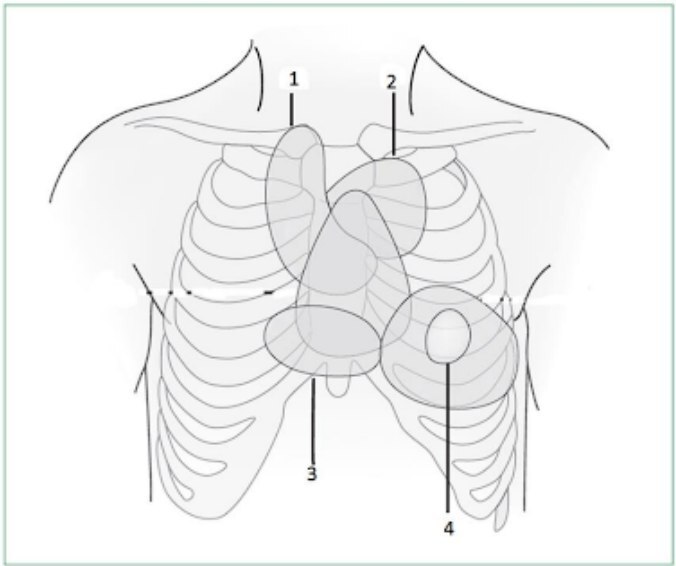

Observe na imagem onde se faz a ausculta dos focos cardíacos decorrentes da Febre REUMÁTICA.

⚠️O 2 é o Pulmonar. O 3 é o Tricúspide.

Na febre reumática secundária ao streptococcus Beta-Hemolitico do grupo A (PYOGENES) as manifestações valvulares cardiológicas mais frequentes podem ser auscultadas nos sítios da ausculta identificados na imagem quais são os números?

1 e 4. Foco aortico e foco mitral respectivamente. SÓ LEMBRANDO QUE A VÁLVULA MAIS ACOMETIDA NA FEBRE REUMÁTICA É A MITRAL E EM SEGUNDO LUGAR VAI SER A VÁLVULA AÓRTICA POR ISSO QUE TEMOS QUE AUSCULTAR ESSES DOIS FOCOS CARDÍACOS.